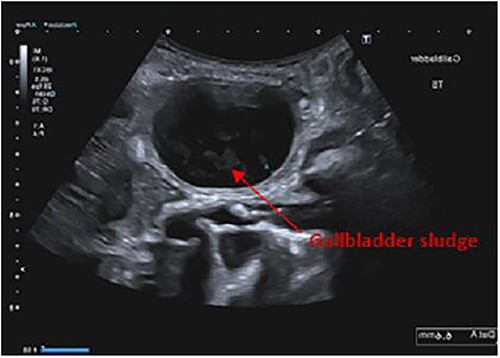

Findings on abdominal ultrasound included a distended gallbladder with thickening of the gallbladder wall up to 7 mm. Definite cholelithiasis was not noted but the gallbladder contained sludge. No dilatation of the intrahepatic or extrahepatic biliary tree was identified (Figs 1 and 2).